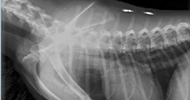

Ultrason Veteriner hekimlikte, hayvan sağlığına ve hastalıklarının teşhisine hizmet eden birçok ekipman rutin olarak kliniklerde kullanılmaya başlanmıştır. Kliniğimizde veteriner hekimler için özel olarak geliştirilmiş Ultrason cihazı ile özellikle karın içi organlarının (idrar kesesi, dalak, böbrek, karaciğer, pankreas, rahim, prostat, mide ve bağırsaklar) muayenesi yapılmakta olup hastalık halleri veya tümöral oluşumlar tespit edilmektedir. Röntgen Röntgen görüntüleme tekniği birçok hastalığın teşhisinde önemli rol oynamaktadır. Kemik yapısındaki anormallikler, kırık ve çıkıklar, eklem hastalıkları eklem üzerinde oluşan anormal üremeler iyi bir röntgen ile teşhis edilirken, karın boşluğuna ait organlardaki yabancı cisimler, tıkanmalar gaz ve düğümlenmeler yine röntgen filmi ile teşhis edilebilir. Ayrıca göğüs ve kalp hastalıklarının tanısında röntgen çok güvenilir ölçüde sonuç vermektedir.